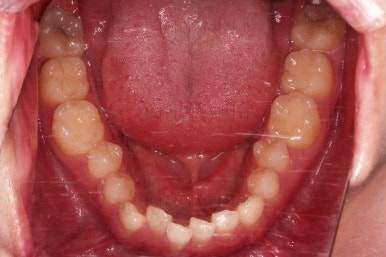

수술 전 교정과정이 거의 마무리 되어 갑니다.

오히려 앞니가 거꾸로 물리는 정도는 더 심해지고요.

수술 직전이 얼굴모습도 가장 주걱턱이 심한 양상으로 됩니다.

농담 삼아 못생겨지면 못생겨질수록 수술이 더 잘될겁니다 라고 말씀 드립니다.